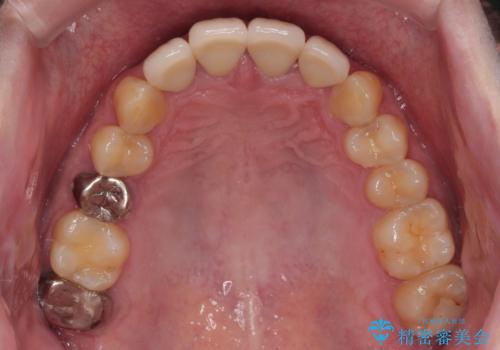

審美面、機能面共に大変満足していただきました。今後は左下の欠損部にインプラント治療を行っていく予定です。